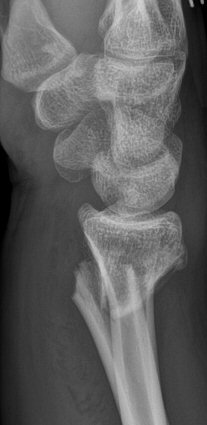

- Colles: extraartikulär, distala fragmentet är felställt dorsalt.

Colles fraktur, dorsalställd extraartikulär